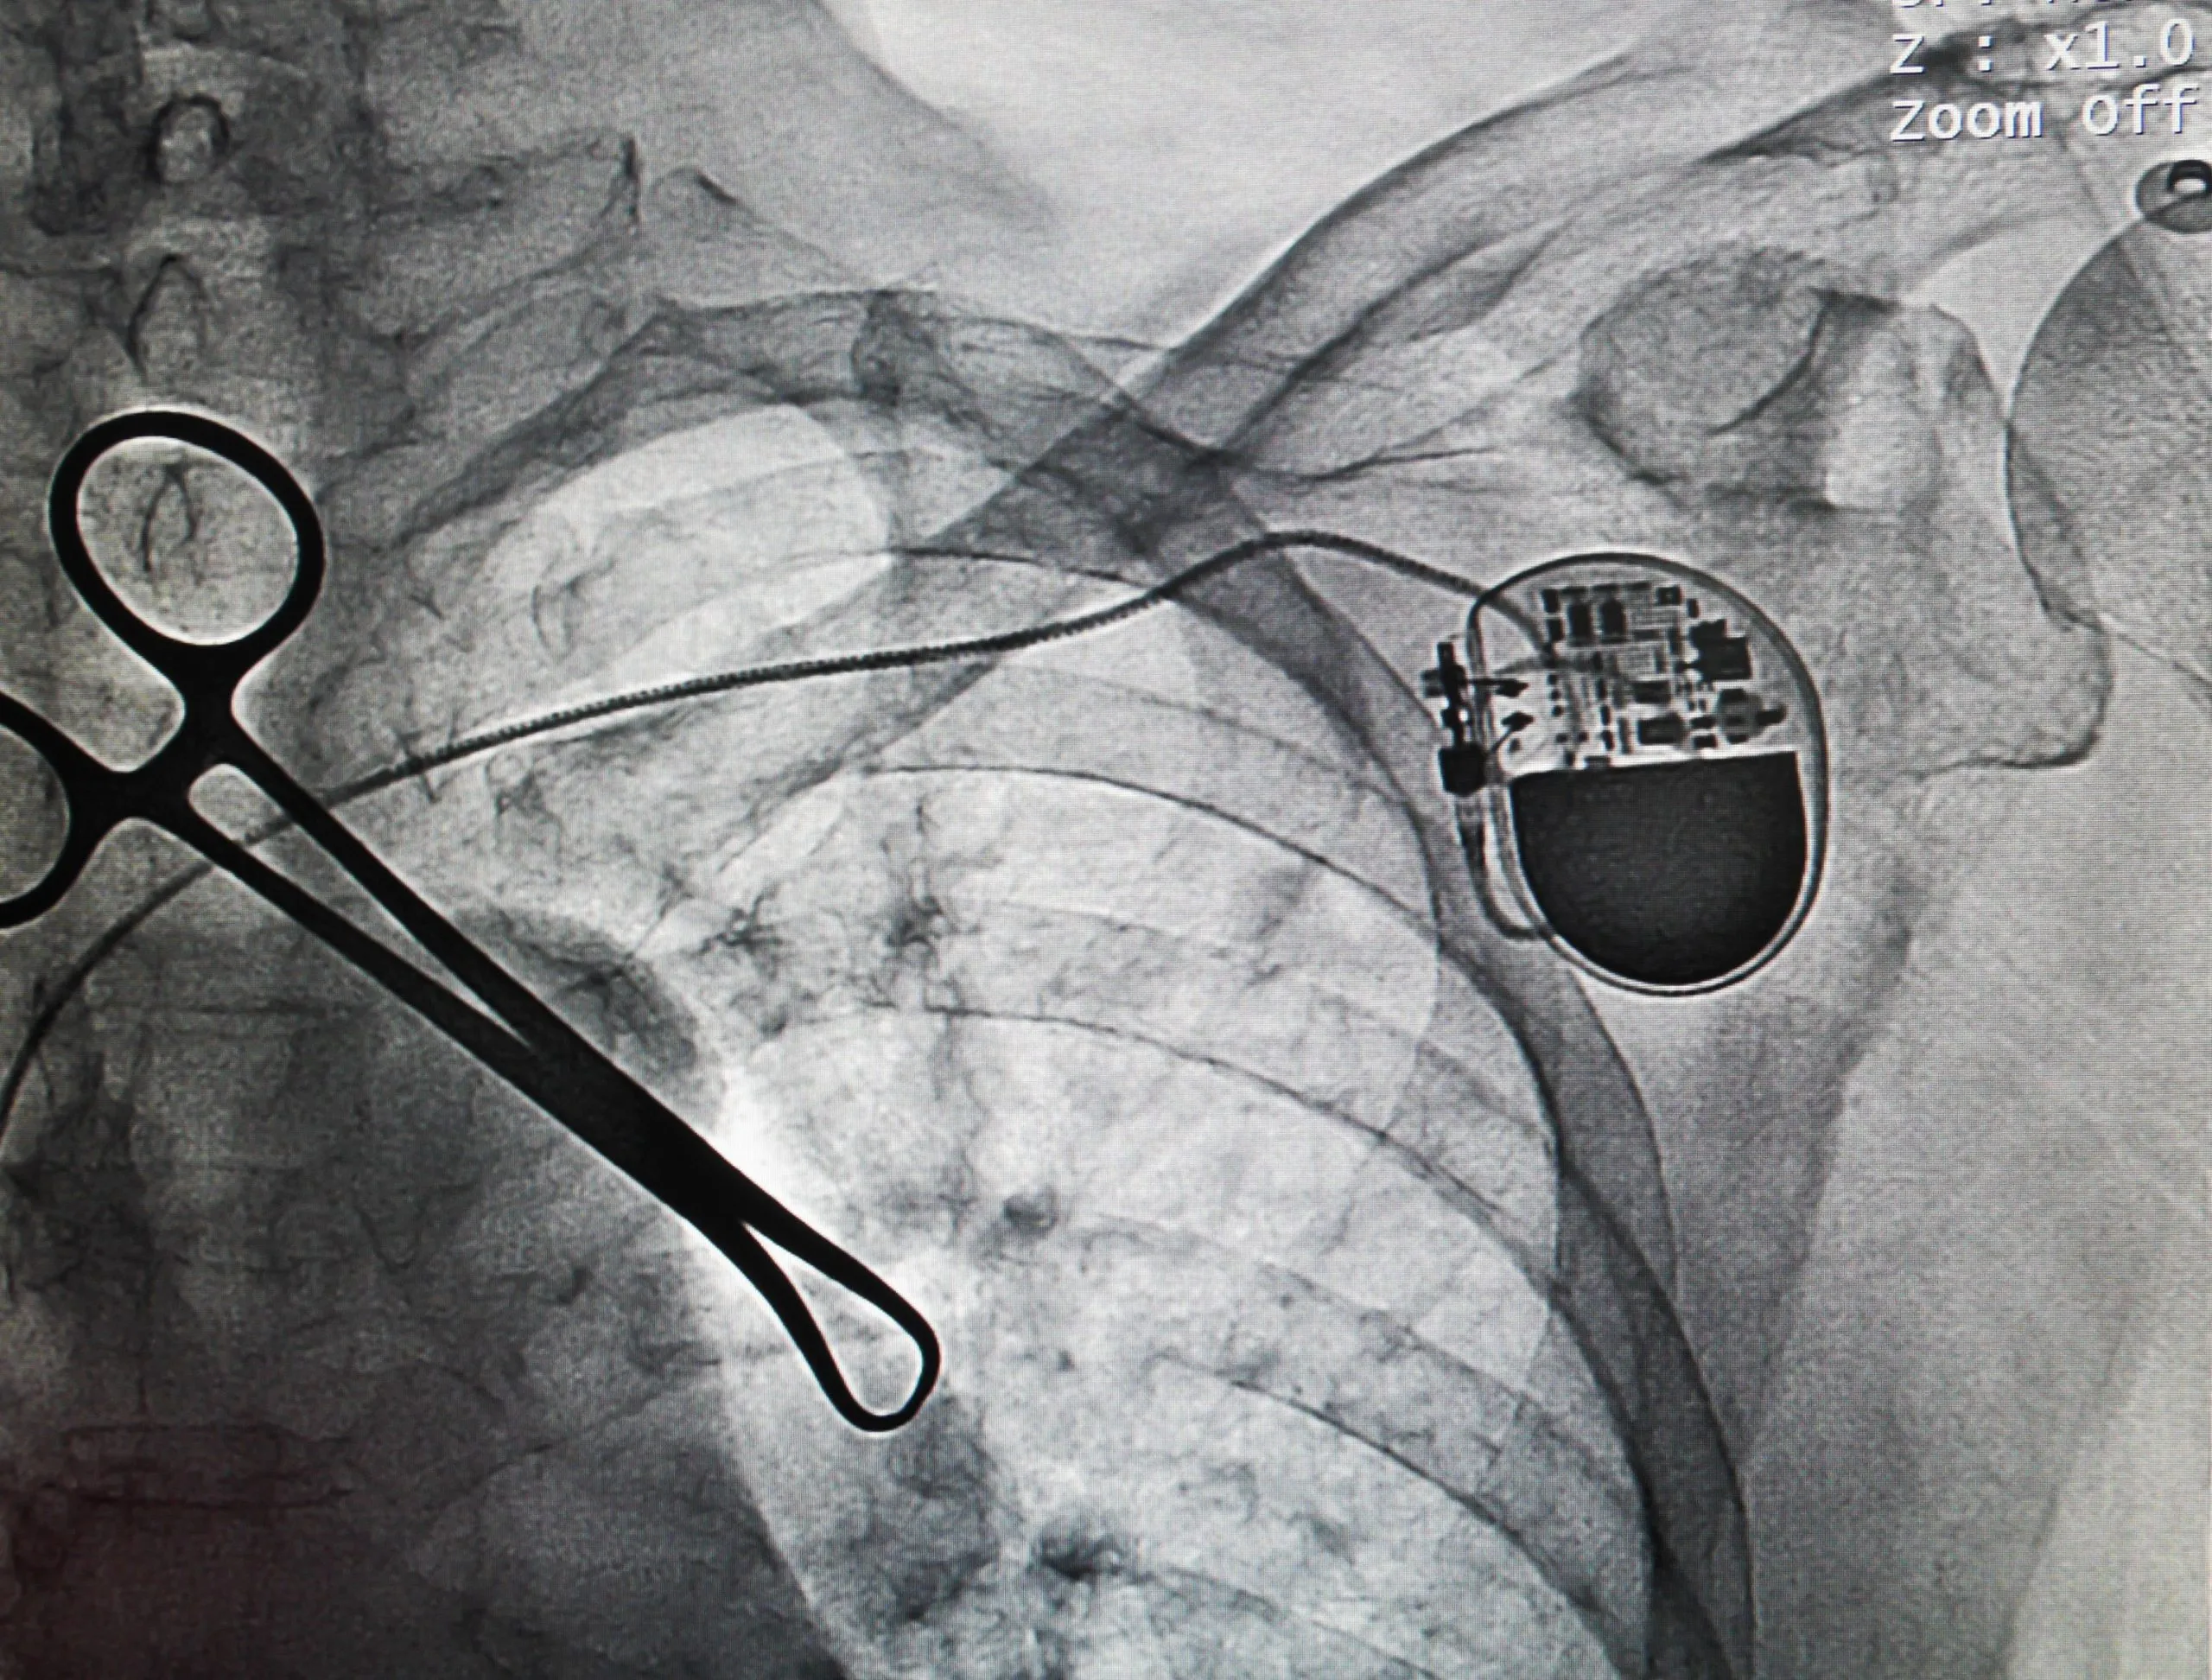

Can I have CT scans and X-rays?

Yes, you can have CT scans and X-rays. However, you should always let your doctor or technologist know that you have a Boston scientific spinal cord stimulator before having any imaging tests.